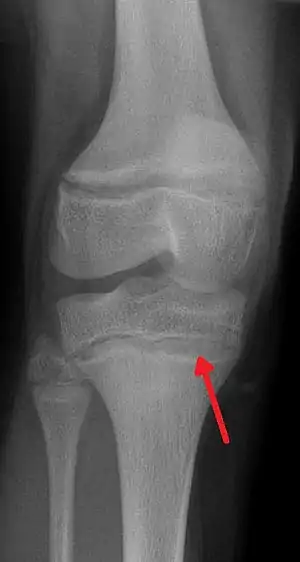

An X ray demonstrating the characteristic finding of lead poisoning in humans—dense metaphyseal lines.